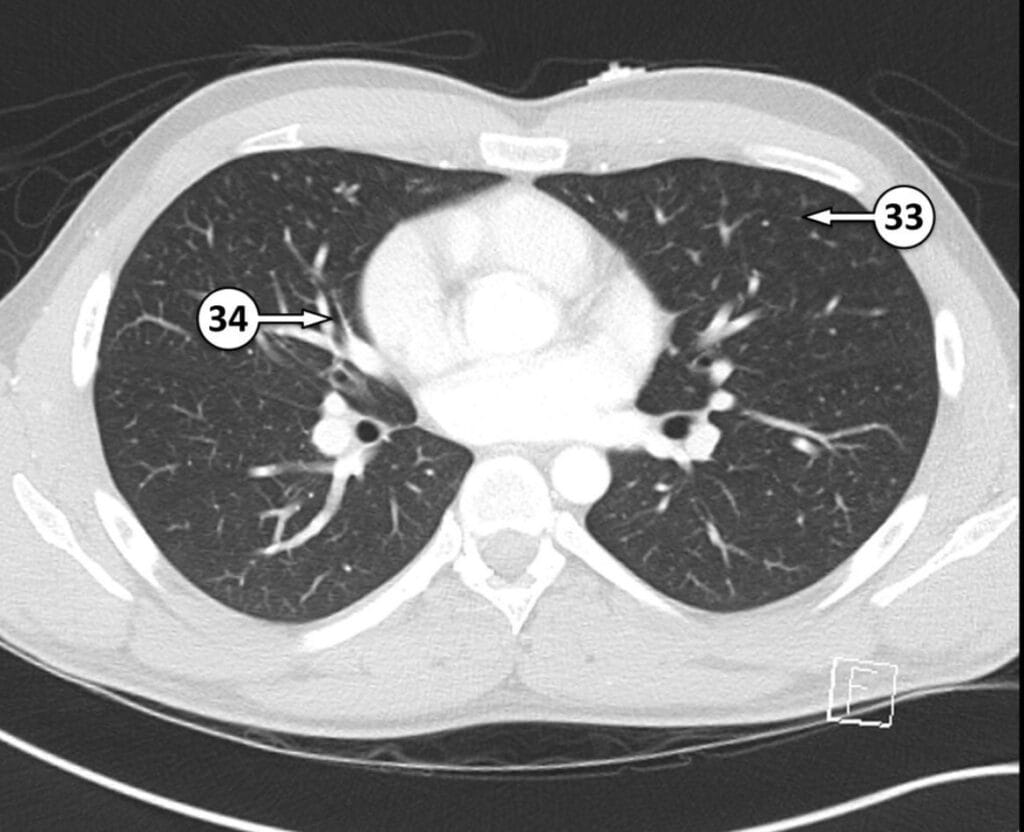

33. superior lingular segment of LUL

34. medial segmental bronchus of RML